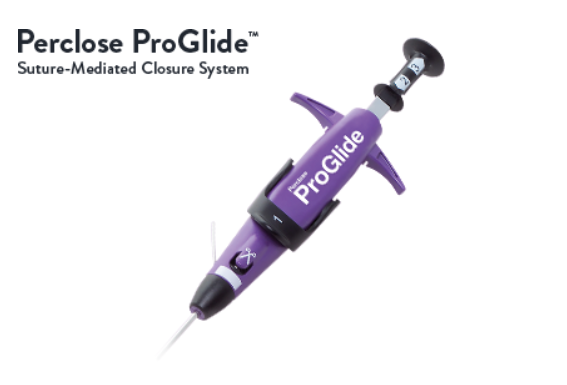

Vessel Closure Solutions

Vessel closure solutions are designed to securely seal arterial access sites after interventional procedures. They help reduce bleeding, promote faster hemostasis, and support quicker patient recovery, enhancing safety and efficiency in minimally invasive cardiovascular interventions.

Vessel Closure Solutions

Vessel closure solutions are designed to securely seal arterial access sites after interventional procedures. They help reduce bleeding, promote faster hemostasis, and support quicker patient recovery, enhancing safety and efficiency in minimally invasive cardiovascular interventions.